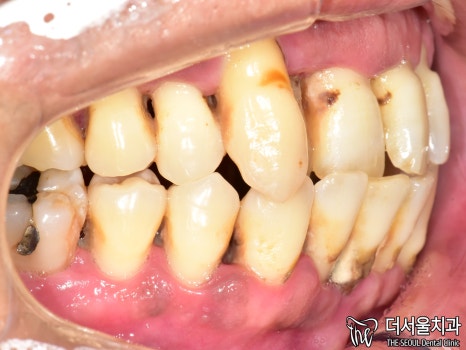

1. 첫 진료

먼저 사진을 보겠습니다.

여러분이 보더라도

구강 상태가 심각하다는 걸 알 수 있습니다.

올바른 교합이 이뤄질 수 없을 뿐더러

치경부 마모증에 쌓여있는 치석에 충치까지

손댈 부분이 너무 많네요.

게다가 구취까지 나고 있었기에

걱정되는 상황이었습니다.